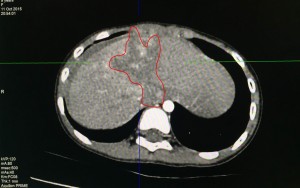

Ngày 04/10/2015, Bệnh viện đa khoa Xuyên Á với sự hỗ trợ của Bệnh viện Chợ Rẫy đã tiến hành thành công ca vi phẫu giải ép vi mạch thần kinh số 5 cho bệnh nhân P.T.V., 65 tuổi, ngụ tại xã Gia Bình, huyện Trảng Bàng, tỉnh Tây Ninh. Đã gần 10 năm nay, […]